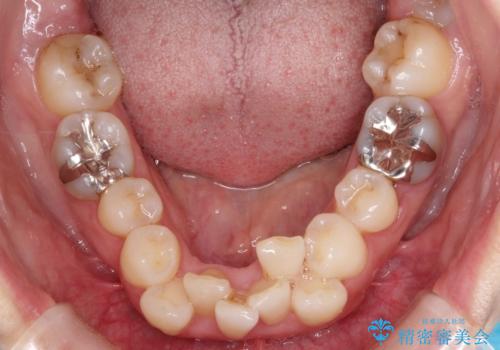

重度のガタガタと出っ歯をワイヤーによる抜歯矯正で整った歯並びへ

- 全体的ながたがたを主訴に来院されました。

上顎の前歯は前方に傾斜して、下顎の前歯は強いガタガタが見られました。

前から4番目の歯を上下左右合計2本抜歯して、歯並びを整える計画としました。

ワイヤー矯正にて治療しました。